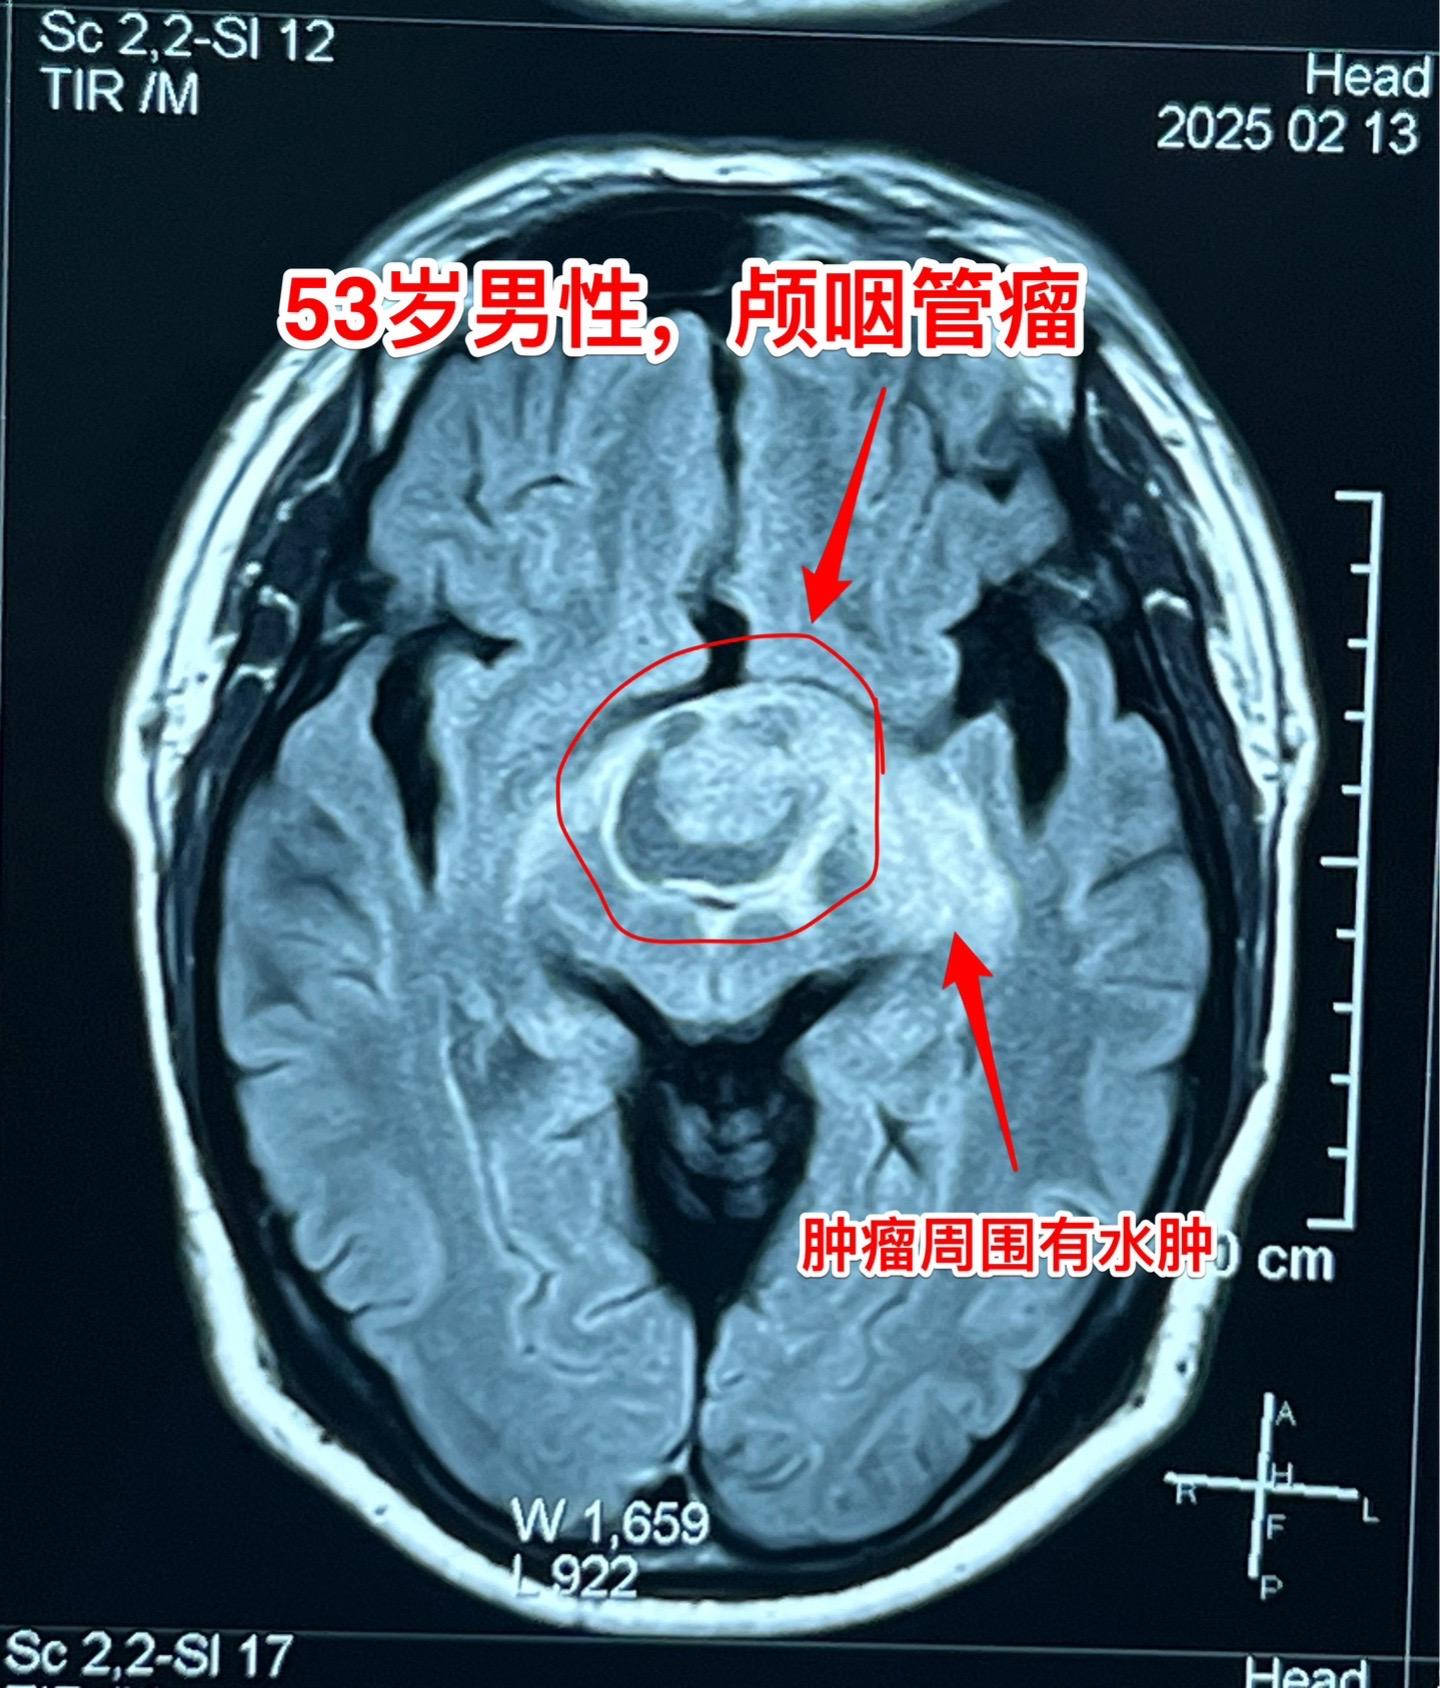

一天两个颅咽管瘤手术医生是很辛苦的 今天按计划作了两个颅咽管瘤手术。这是第二个病人,云南省文山州的警察,因记忆力差、爱睡觉、视力下降到医院检查发现了颅咽管瘤,是乳头型颅咽管瘤。 今天晚上九点多钟颅咽管瘤完全切除了,同时发现前交通动脉有个小动脉瘤,征得家人同意后作了动脉瘤夹闭术。期望病人一切都好!